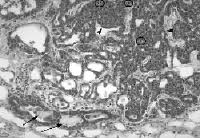

These breast cancer tumors are also known as non-invasive ductal carcinomas. They have characteristics that project malignancy when viewed with the help of a microscope. These breast cancer tumors are usually very hard to evaluate with regard to their tendency to multiply or divide. DCISs are breast cancer tumors that have not yet penetrated the tissues around the site itself but you have to remember that these may be very well the starters or precursors of breast cancer tumors that are invasive. Those breast cancer tumors that are high-grade DCIS become invasive every year. At present, it is still being discussed id DCIS could be treated by mastectomy, with the use of radiation, or without radiation.